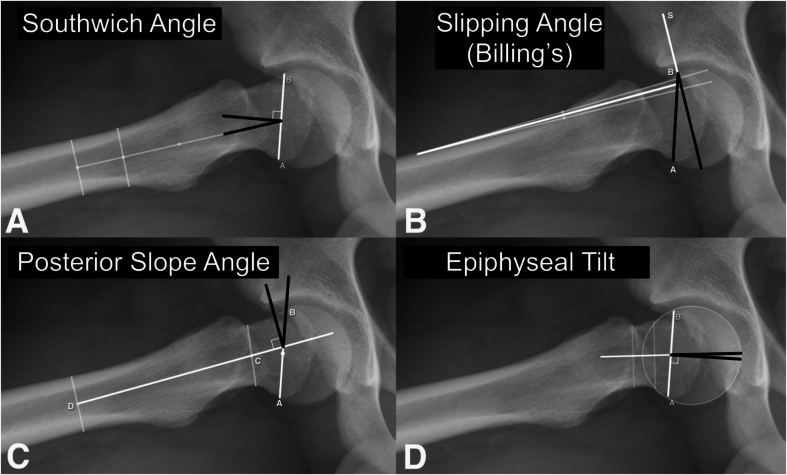

Methods: We assessed frog-leg radiographs from 312 patients with unilateral SCFE, measuring the Billings, Southwick, Posterior Sloping Angle (PSA), and tilt angles. Seventy patients (22%) experienced contralateral slips, with a median follow-up of 42 months (range, 18-70 months). Radiographs were evaluated independently by four raters at two separate time points. The radiographic parameters were compared between patients who developed contralateral slips and those who did not, and the diagnostic utility of each radiographic measure was assessed through receiver operating characteristic (ROC) curve analysis, with area under the ROC curve (AUC) values calculated for each method. Sensitivity, specificity, and predictive values were also determined using literature-based cutoffs for the angles (tilt angle >10°, Billings >12°, PSA >14°, Southwick >12°).

Key concepts: 1.Radiographic Predictive Measurements for Contralateral SCFE: The study evaluates the diagnostic utility of various radiographic angles (Epiphyseal Tilt, Billing's, Posterior Sloping, and Southwick angle) in predicting contralateral slips in unilateral SCFE cases, highlighting their sensitivity, specificity, and clinical implications.2.Interrater and Intrarater Reliability of radiographic measurements: The study demonstrates excellent interrater and intrarater reliability across all radiographic measurements, emphasizing the consistency and reproducibility of these methods for clinical use.3.Limitations of Current Predictive Radiographic Measurements: The study highlights the limitations of existing radiographic methods in achieving perfect predictive accuracy, advocating for future research to explore advanced imaging techniques like 3D MRI or CT to improve the identification of contralateral slip risk.4.Trade-Off Between Sensitivity and Specificity: The findings emphasize the critical trade-off between minimizing missed contralateral slips versus avoiding unnecessary prophylactic pinning.5.Clinical Decision-Making Guidance: By providing detailed accuracy and predictive values for each measurement, the study offers practical guidance for orthopaedic surgeon. Surgeons who aim to minimize the risk of missing a contralateral slip should consider using the Billings angle with a cutoff of 12°, accepting that this may lead to some unnecessary pinning of hips that would not have slipped. Conversely, those who prioritize avoiding unnecessary surgery may prefer the tilt angle with a cutoff of 10°, understanding that this approach could result in missing some hips that will later develop a slip.